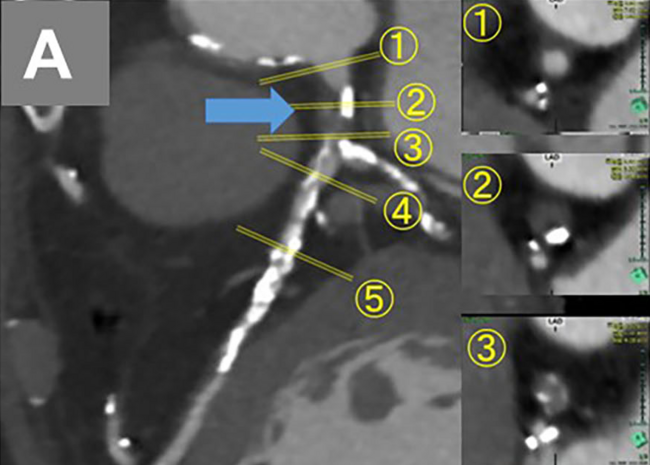

Coronary Intervention in Chronic Total Occlusion in Left Main Coronary Artery

Video 3. The guidewire penetrating the left main occlusion lesion and crossing to the left circumflex artery.

Video Supplement to "Coronary Intervention in Chronic Total Occlusion in Left Main Coronary Artery" (Clinical Image).